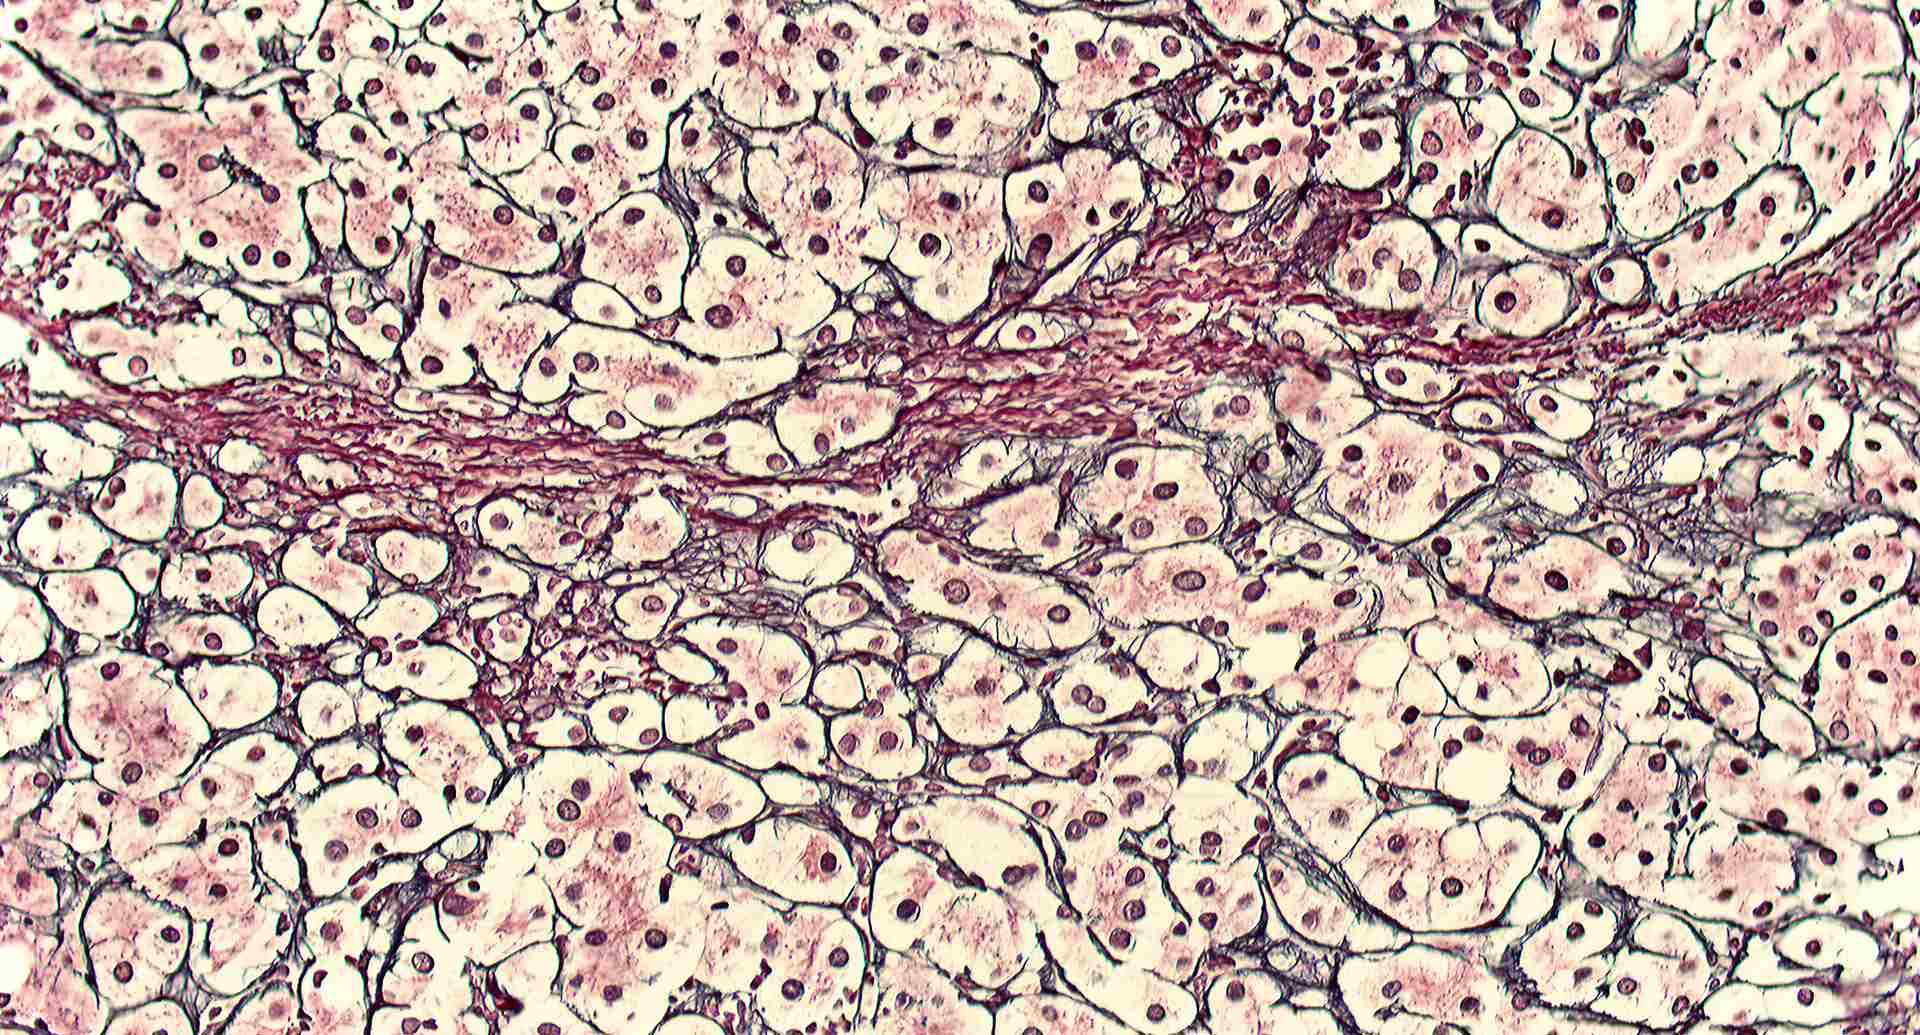

標本7